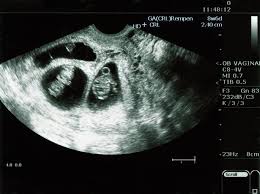

An ultrasound scan is the only way to confirm that you re pregnant with twins mcaslan fraser nd nice 2011. After week 6 0 both hearts should be beating. As the babies grow there tends to be more movement and light flutters felt in the abdomen by the pregnant woman. Regardless elevated beta hcg levels in early pregnancy isn t a proper way to detect twins.

The earliest you re likely to find out is between 10 weeks and 14 weeks when you have your dating scan mcaslan fraser nd nhs 2019 nice 2011. If they are mo di or mo mo twins you have to wait until 6 full weeks have passed. All fraternal twins and 20 to 30 percent of identical twins have separate placentas. Generally when you are pregnant with twins fetal movements become more noticeable at weeks 18 through 20 of pregnancy and the same is true in singleton pregnancies al khan says.